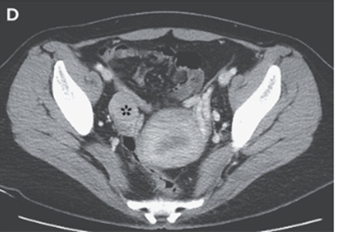

また右卵巣には最大直径44mmの固形腫瘤(下記星印)を認めた。